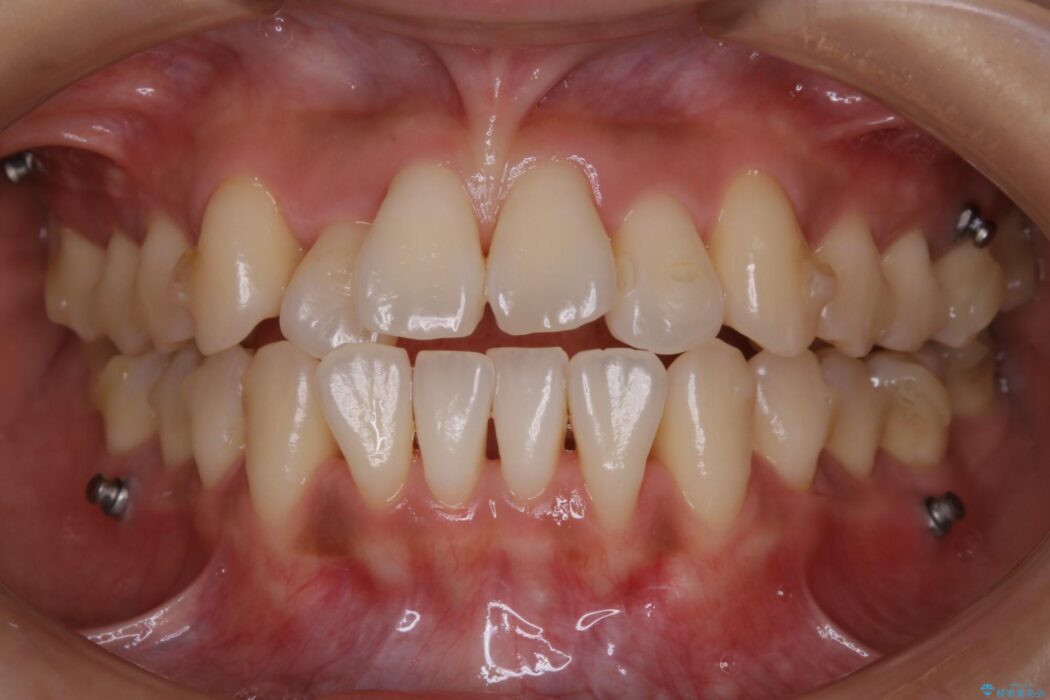

よってマイクロインプラントを用い、奥歯から順番に遠心移動させることによってスペースを確保することにしました。

歯を後方に移動させてスペースを確保する場合、マウスピースの装着時間に加えて装着時の適合度が良い状態に保たれているかが鍵となります。

歯は戻ろうとする力が強いためマウスピースの装着をしっかりしていただけなかった場合は、作り直しや治療の長期化につながってしまう可能性があります。